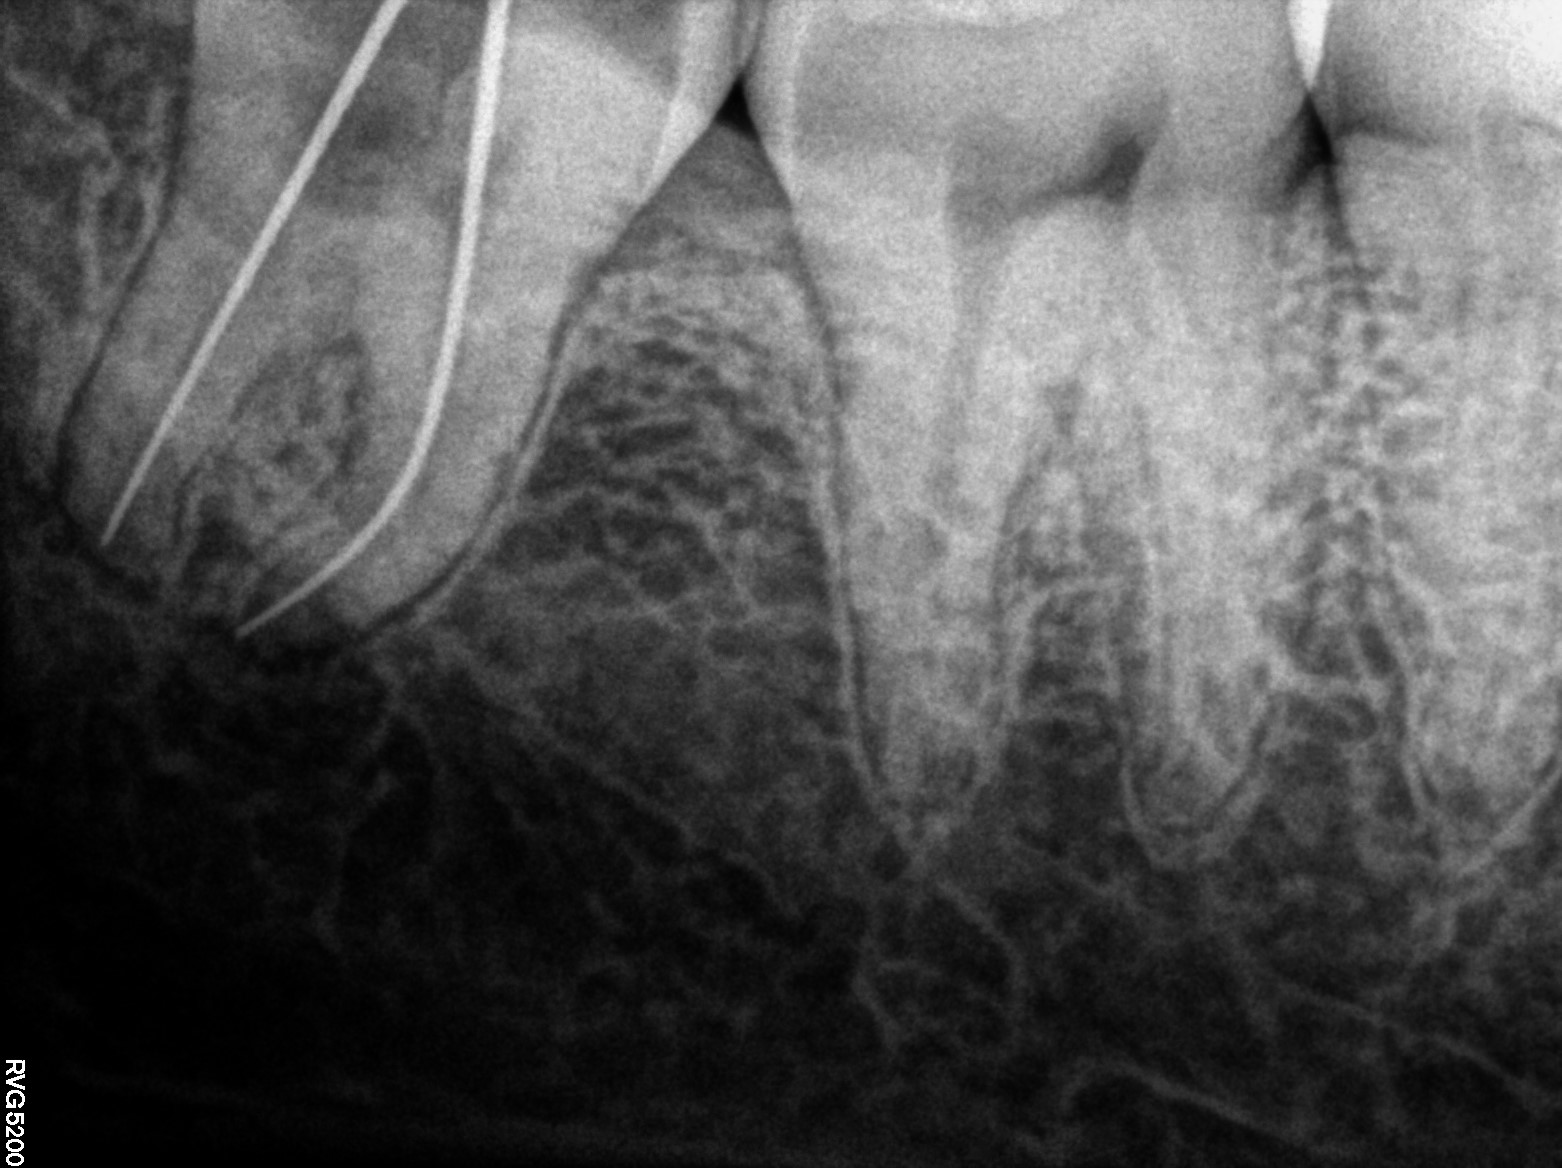

Dental Radiographs FHIR: DocumentReference · LOINC 24641-7

R74.jpg

24641-7